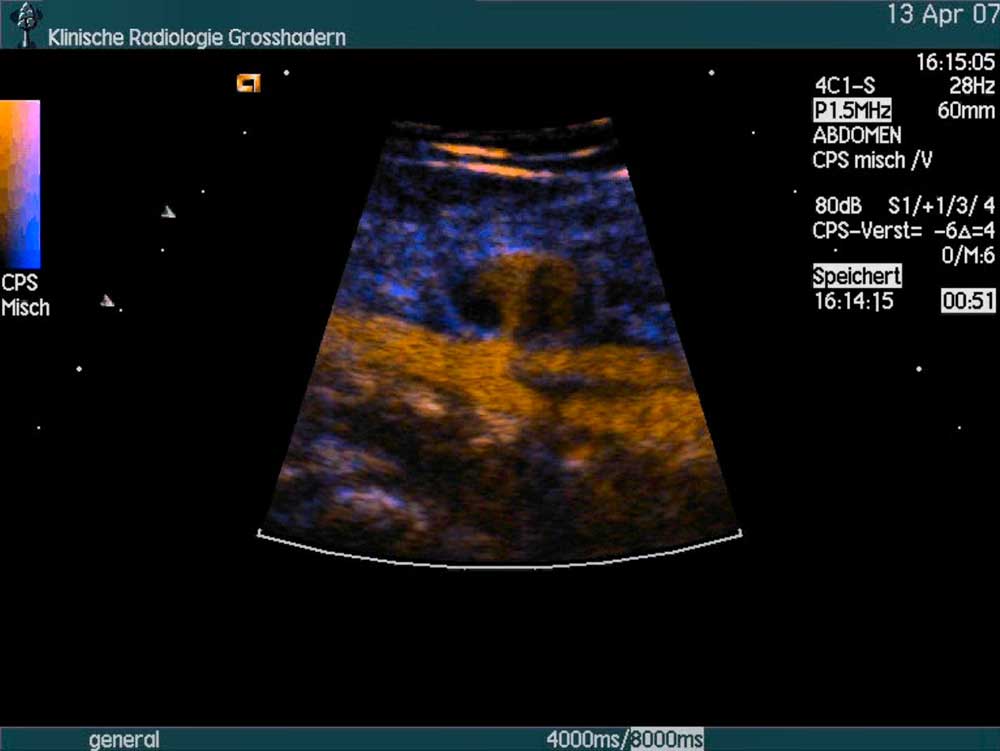

A Contrast Ultrasound Agent can also be visualised in the microcirculation of parenchymal organs, resulting in an enhancement of the vascular compartment without extravasation into the interstitial fluid. This allows an improved characterisation of breast and liver lesions.